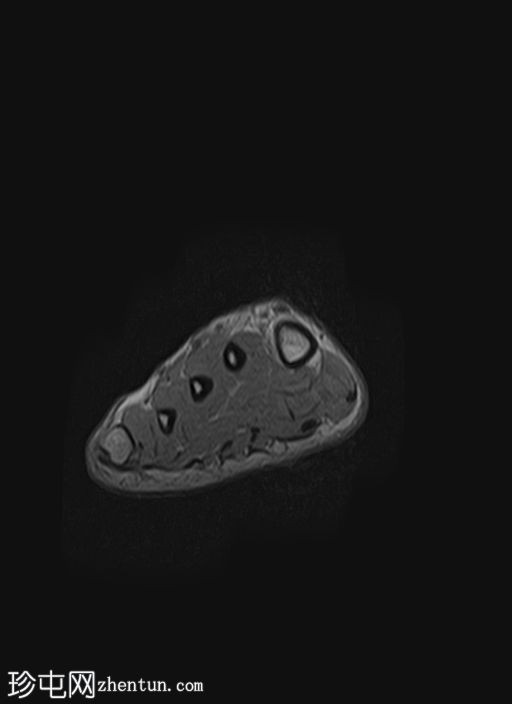

PD脂肪抑制

轴位

质子密度(PD)脂肪抑制像显示第二跖骨干骨髓水肿,伴骨膜及周围软组织水肿。未见明确的皮质骨折线。

第二跖骨应力性骨折,根据Fredericson分级,MRI分级为3级,伴骨膜及周围软组织水肿。